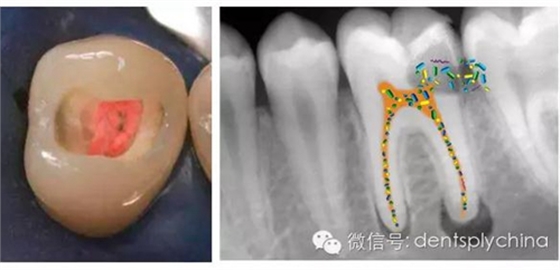

根管治療-消除根尖周感染

那么您意識到根管治療后冠部封閉在其中的重要性了嗎?

根管治療成功率和嚴(yán)密的冠部封閉密切相關(guān)

"對于控制根尖周感染而言,冠部修復(fù)的質(zhì)量比根管治療的質(zhì)量更重要。"

然而,巨大的收縮應(yīng)力導(dǎo)致醫(yī)生很難獲得真正可靠地邊緣封閉。

超低收縮應(yīng)力、4mm一層充填的SDR可以極大的改善冠部封閉